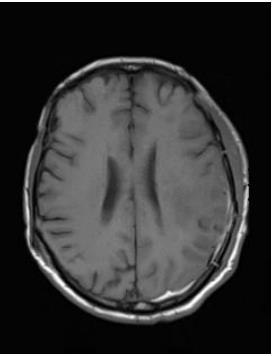

• 肿瘤样脱髓鞘病变报道3例

2023, 48(5):614-617. DOI: 10.13406/j.cnki.cyxb.003183

摘要 (95) HTML (24) PDF 1.29 M (241) 评论 (0) 收藏

摘要: